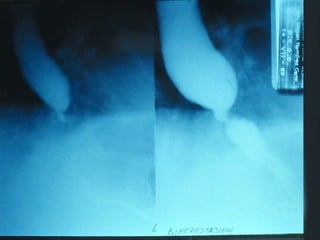

SEGD ENFERMEDADES DEL ESTOMAGO Y DUODENO El duodeno se divide en cuatro porciones; que se extienden desde el píloro hasta el ligamento de Treitz. La primera porción se denomina bulbo duodenal.

SEGD ENFERMEDADES DELESTOMAGO Y DUODENO El duodeno se divide en cuatro porciones; que se extienden desde el píloro hasta el ligamento de Treitz. La primera porción se denomina bulbo duodenal.